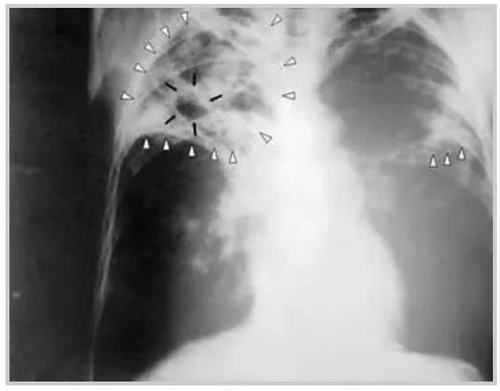

肺结核咳痰带血丝图片,肺结核初期痰的图片

更新 a 粟粒性肺结核 b 含铁血黄素沉着 c 弥漫

空洞型肺结核